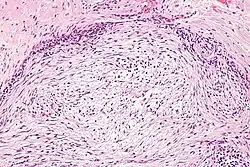

Micrograph of nodular fasciitis showing the haphazard arrangement of cells (tissue culture-like pattern). H&E stain.

The microscopic histopathology of hematoxylin and eosin stained nodular fasciitis tumors consists of spindle-shaped myofibroblastic cells.[8] These cells are in a myxoid or a collagenous (high content of collagen fibers) tissue background. The neoplastic myofibroblasts are arranged in whorls and/or short bundles. These cells may show high rates of replicating as judged by their mitotic index, but these mitoses are normal in appearance. The tumor tissues often contain red blood cells, lymphocytes, and giant osteoclast-like cells, and may contain sites of bone-like tissue.[10] NF is sometimes classified into three subtypes based on its predominant histopathological pattern: myxoid or reactive (type I), cellular (type II), and fibrous (type III).[4] These patterns appear related to the duration of the lesion, with the myxoid variant tending to have the shortest duration and the cellular and fibrous variants tending to have progressively longer durations.[14] Immunohistochemical analyses indicate that the cells in NF usually express smooth muscle actin, muscle specific actin, and vimentin proteins but generally do not express CD34, S-100 protein, desmin, trypsin, factor VIII, F4/80, or HLA-DR1 proteins.[10] Uncommonly, the cells in NF tumors express the CD68 (a histiocyte-specific marker) protein.[4]